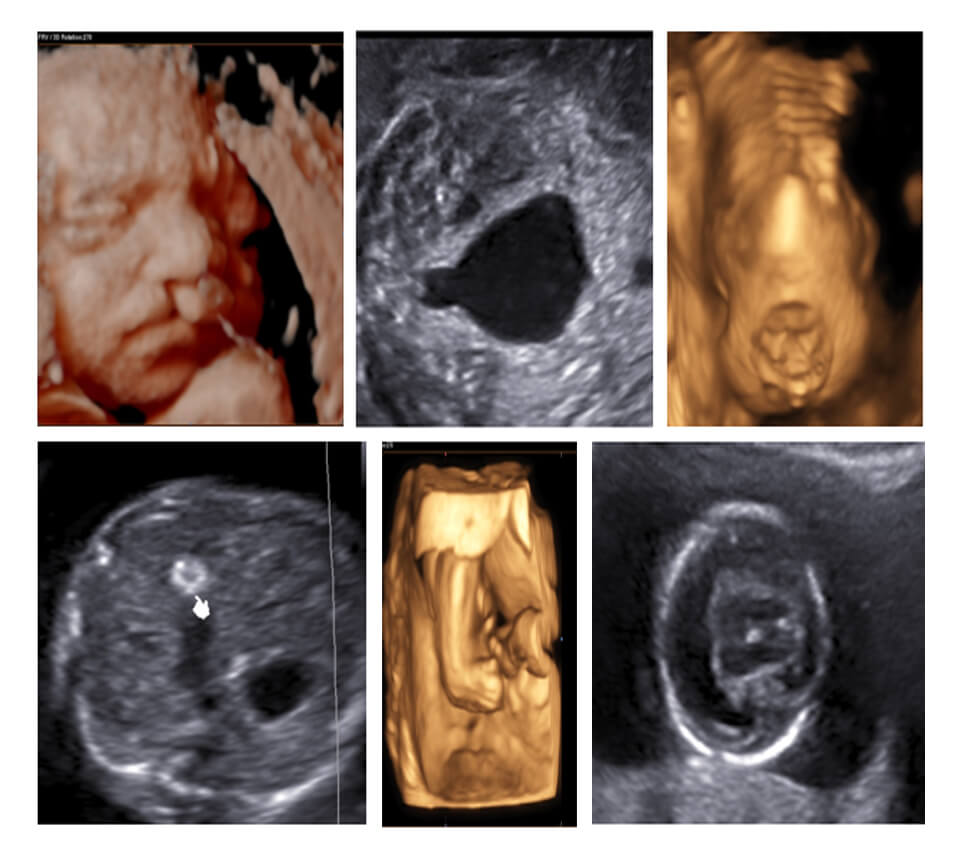

FIRST TRIMESTER (11-14 WEEKS) USG

Week 2 FIRST TRIMESTER NORMAL

Week 3 SECOND TRIMESTER NORMAL & FETAL SPINE

Week 4 FETAL CRANIUM

Week 5 FETAL THORAX

Week 6 FETAL ABDOMEN(GIT) & FACE

Week 7 FETAL ABDOMEN (URINARY)

Week 8 FETAL SKELETAL

Week 9 FETAL HEART

Week 10 GENETIC SCAN